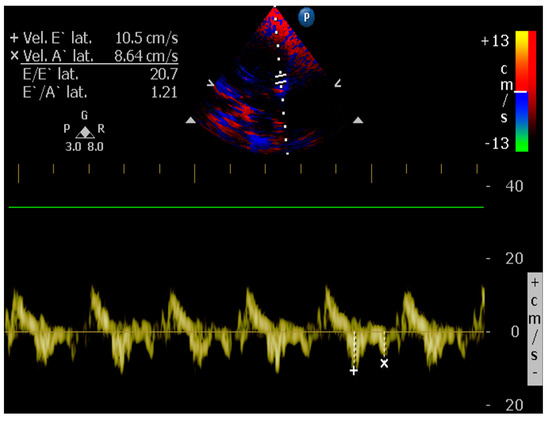

4.8.8. E/é Ratio of the Mitral Annulus

- Santos, M.; Rivero, J.; McCullough, S.D.; West, E.; Opotowsky, A.R.; Waxman, A.B.; Systrom, D.M.; Shah, A.M. E/e’ Ratio in Patients with Unexplained Dyspnea: Lack of Accuracy in Estimating Left Ventricular Filling Pressure. Circ. Heart Fail. 2015, 8, 749–756. [Google Scholar] [CrossRef]